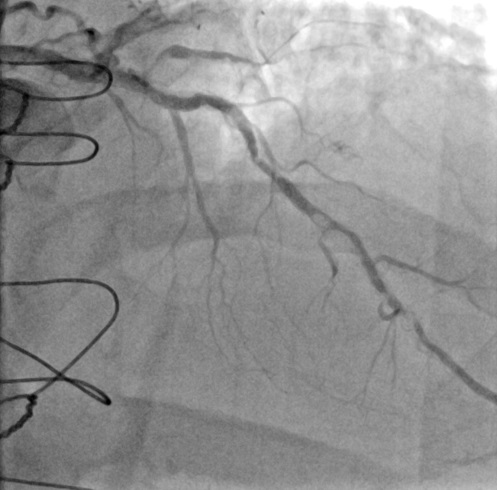

A 73-year-old man presented with exertional angina and anterior ischemia on stress testing. He had undergone prior coronary artery bypass surgery and multiple percutaneous coronary interventions (PCI). Coronary angiography demonstrated multiple severe and heavily calcified stenoses in the mid- and distal left anterior descending artery (LAD) within previously implanted stents (Figure 1, Video 1).